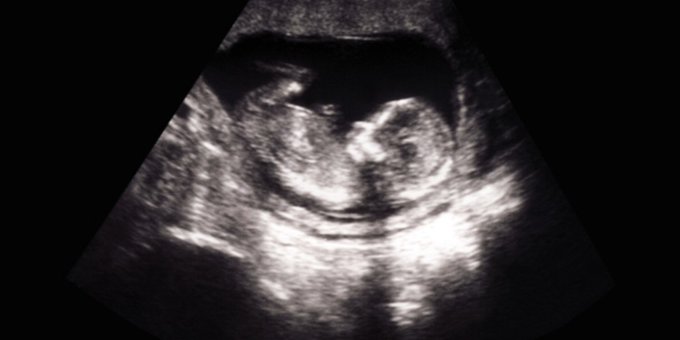

Un defecto congénito ocurre cuando un bebé se está desarrollando en el útero de la madre. Aquí lo que debes saber ow.ly/gxFL50xTLxJ #BirthDefectsPreventionMonth